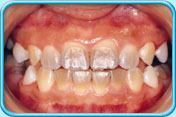

由於恆齒的琺瑯質是稍微透明的,內層黃色的象牙質就透現出來,所以恆齒會呈微黃色。隨年紀漸長,象牙質不斷增厚,牙齒亦會變得比較黃,這情況是正常的。

呈微黃色的恆齒乳齒的琺瑯質不及恆齒的琺瑯質那般透明,因此乳齒呈乳白色。